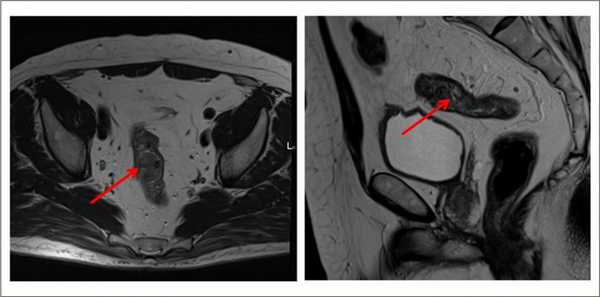

Для определения распространенности злокачественного процесса. Можно выполнять абдоминально - через брюшную стенку, и трансректально - через анальное отверстие.

Выявляет даже небольшие по размеру патологические очаги, метастазы и инвазию опухоли в соседние органы, ее топографическое положение относительно других структур. Метод безопасен, не создает радиационную нагрузку, в отличие от КТ.